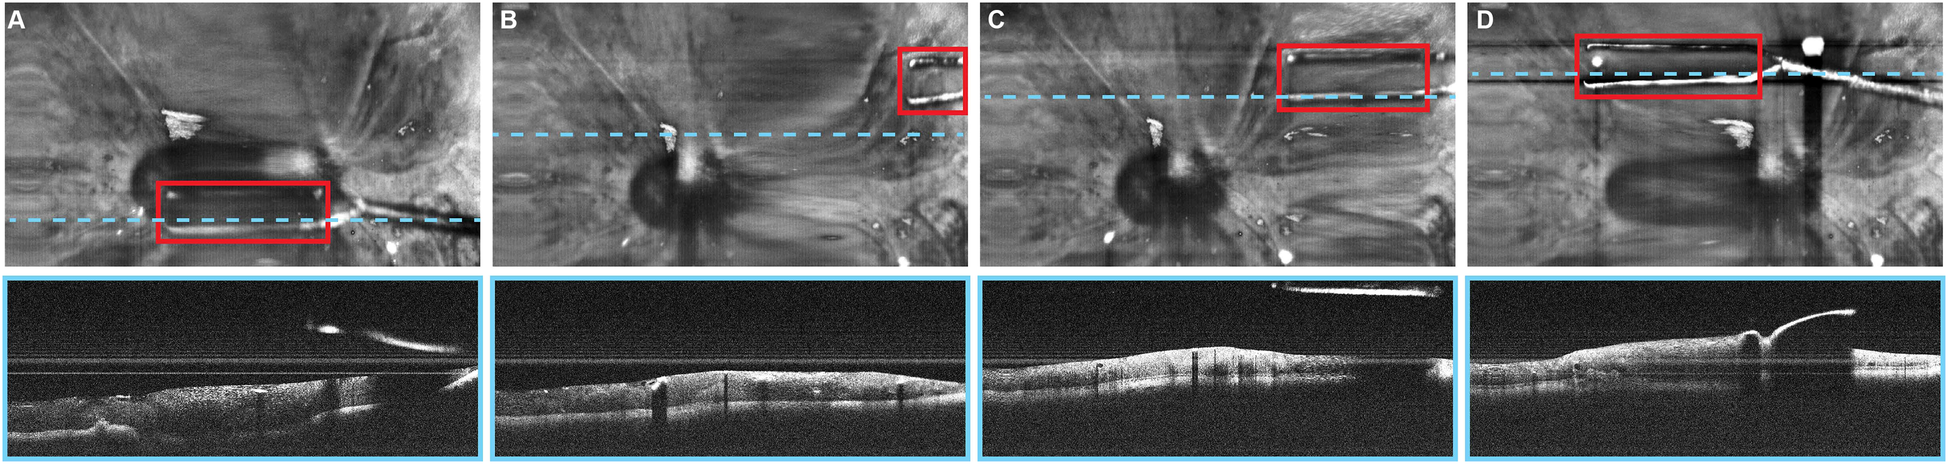

Automated instrument tracking using SECTR has also been proposed. This method was used in 2 studies by Tang et al. (39, 47), in which the movements of the 25G ILM forceps, a surgical instrument, were tracked by spectrally encoded reflectometry. The forceps were tracked by training a CNN, allowing 4-dimensional (4D) visualization of surgical motion during ophthalmological surgeries (Figure 6) (39, 47).

Automated instrument-tracking using SECTR. Tang et al. (39) trained a CNN to track 25G ILM forceps, a surgical instrument, to allow 4D visualization of the surgical motion during ophthalmologic surgeries. (A) Five-averaged SER image and representative OCT image demonstrating the tip of the forceps (red box) in an ex vivo bovine eye. Movement of the instrument out of the OCT plane (blue dashed line) and adaptive sampling can be seen on (B–D). CNN, convolutional neural network; OCT, optic coherence tomography; SECTR, spectrally encoded coherence tomography and reflectometry; SER, spectrally encoded reflectometry; 4D, four-dimensional. Used with permission from Tang E, El-Haddad M, Malone JD, et al. Automated instrument-tracking using deep-learning-based adaptively-sampled spectrally encoded coherence tomography and reflectometry (SECTR). Investigative Ophthalmology & Visual Science. 2019;60(9):1276-1276.